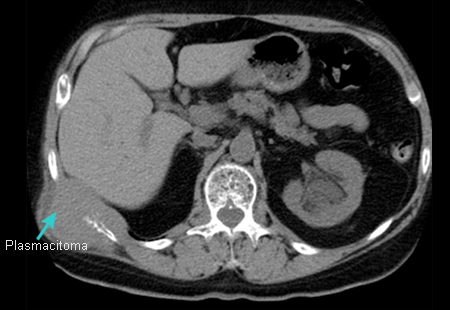

Avaliação de gamopatias monoclonais

Plasmacitoma

Do acervo pessoal do Dr. Kumar